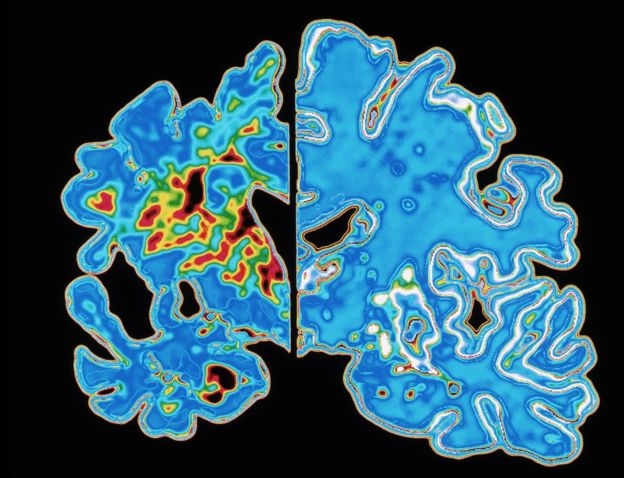

치매 환자의 뇌(왼쪽)과 건강한 이의 뇌.